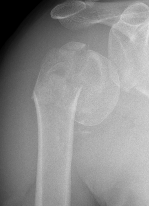

Deforming Forces

| 2 part fracture | Greater tuberosity fracture | Lesser tuberosity fracture |

|---|---|---|

|

Pectoralis major displaces shaft medially Head internally rotated by SSC |

Fragment pulled postero-superior Combination of supraspinatus / infraspinatus / Teres minor |

Displaced medially by subscapularis |